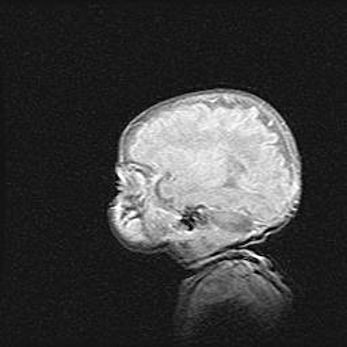

Неполная лизэнцефалия (пахигирия). Открытая гидроцефалия.

Возраст: 17 дней

Вес: 3110 г

Пол: мужской

Окружность головы: 33,5 см

Срок гестации: 35-36 недель

Лизэнцефалия—недоразвитие корковой пластинки и мозговых извилин в результате нарушения миграции нейронов коры. Поверхность мозговых полушарий гладкая. Микроскопически выявляется отсутствие нормальных слоев коры и скопление групп нейронов в подкорковом белом веществе.

Пахигирия—уменьшение числа вторичных извилин. В пораженном полушарии нервные клетки образуют толстый недифференцированный слой с неправильно расположенными нервными волокнами и группами гетеротопных клеток. Нервные клетки незрелые. Белое вещество истончено. При этом нередко аномально развит корково-спинномозговой путь.